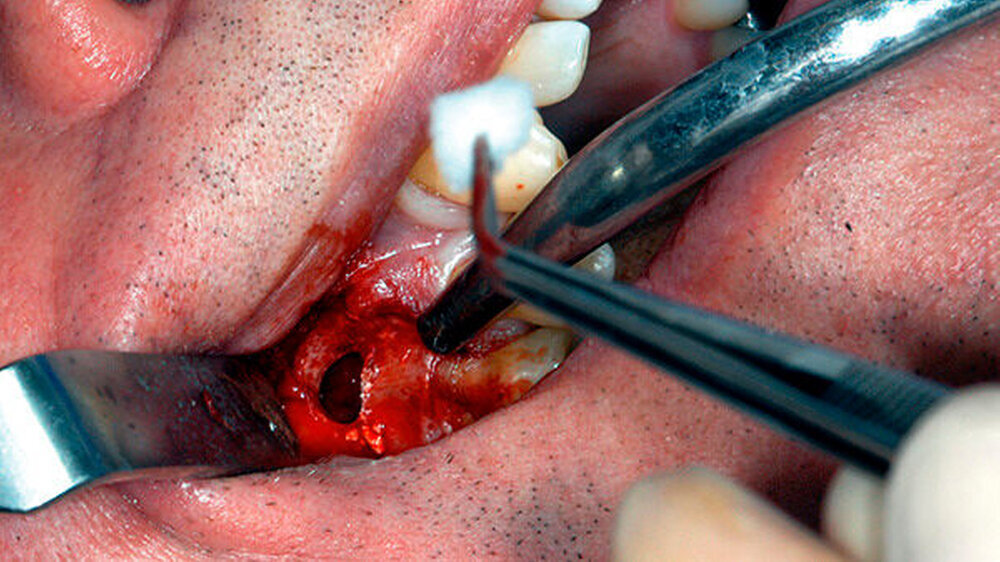

Ein 61-jähriger Patient stellte sich mit Schmerzen und einer Schwellung (Durchmesser etwa 1 cm) in der Umschlagfalte des rechten Oberkiefers regio 16 in der Poliklinik für Zahnerhaltung des Universitätsklinikums Münster vor. Zahn 16 zeigte sich in der Sensibilitätstestung mit CO2-Schnee negativ und in der Perkussionsprobe positiv.

Er berichtete, dass an diesem Zahn ungefähr ein Jahr zuvor eine Wurzelkanalbehandlung alio loco durchgeführt worden war. Das angefertigte Röntgenbild (Abbildung 1) zeigte eine apikale Aufhellung und ein frakturiertes Wurzelkanalinstrument, das vermutlich über den Apex des mesiobukkalen Wurzelkanals herausragte. Die Füllung aller vier Wurzelkanäle erschien röntgendicht, wandständig und ohne Zeichen von Porositäten oder Lufteinschlüssen.

Am nächsten Tag und dann vier Tage nach der Erstversorgung kam der Patient zur Wundspülung und zum Austausch des Iodoformstreifens. An beiden Tagen berichtete der Patient davon, beschwerdefrei zu sein. Ein Austritt von Pus konnte nicht mehr beobachtet werden. Weitere drei Tage später wurde - nach eingehender Beratung und Aufklärung des Patienten - eine Wurzelspitzenresektion geplant. Nach terminaler Anästhesie wurde ein trapezförmiger mukogingivaler Lappen in regio 16 präpariert.

Um die mesiobukkale Wurzel freizulegen, wurde der Knochen darüber entsprechend entfernt (Abbildung 2) und eine Wurzelspitzenresektion an der mesiobukkalen Wurzel Zahn 16 durchgeführt. Das Granulationsgewebe konnte vollständig entfernt werden und wurde für eine histopathologische Untersuchung eingeschickt.